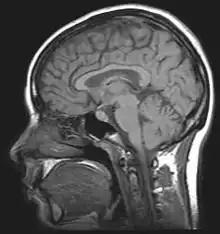

Image of brain MRI.

MRI

An MRI (magnetic resonance imaging) scan is an imaging test that uses powerful magnets and radio waves to create pictures of the body. It does not use radiation. Single MRI images are called slices. The images can be stored on a computer or printed on film. One exam produces dozens or sometimes hundreds of images. To locate nerve palsy, MRI is used by physicians to detect the position and location of damaged peroneal nerve.[11]